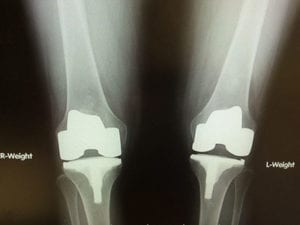

Joint Replacement: What are Artificial Joints Made Out of?

Every day, people all over the world need to get some form of joint replacement. In the United States alone, a whopping one million people will have a total joint replacement procedure, and the numbers are expected to rise above four million per year in the next two decades. For an aging Read More